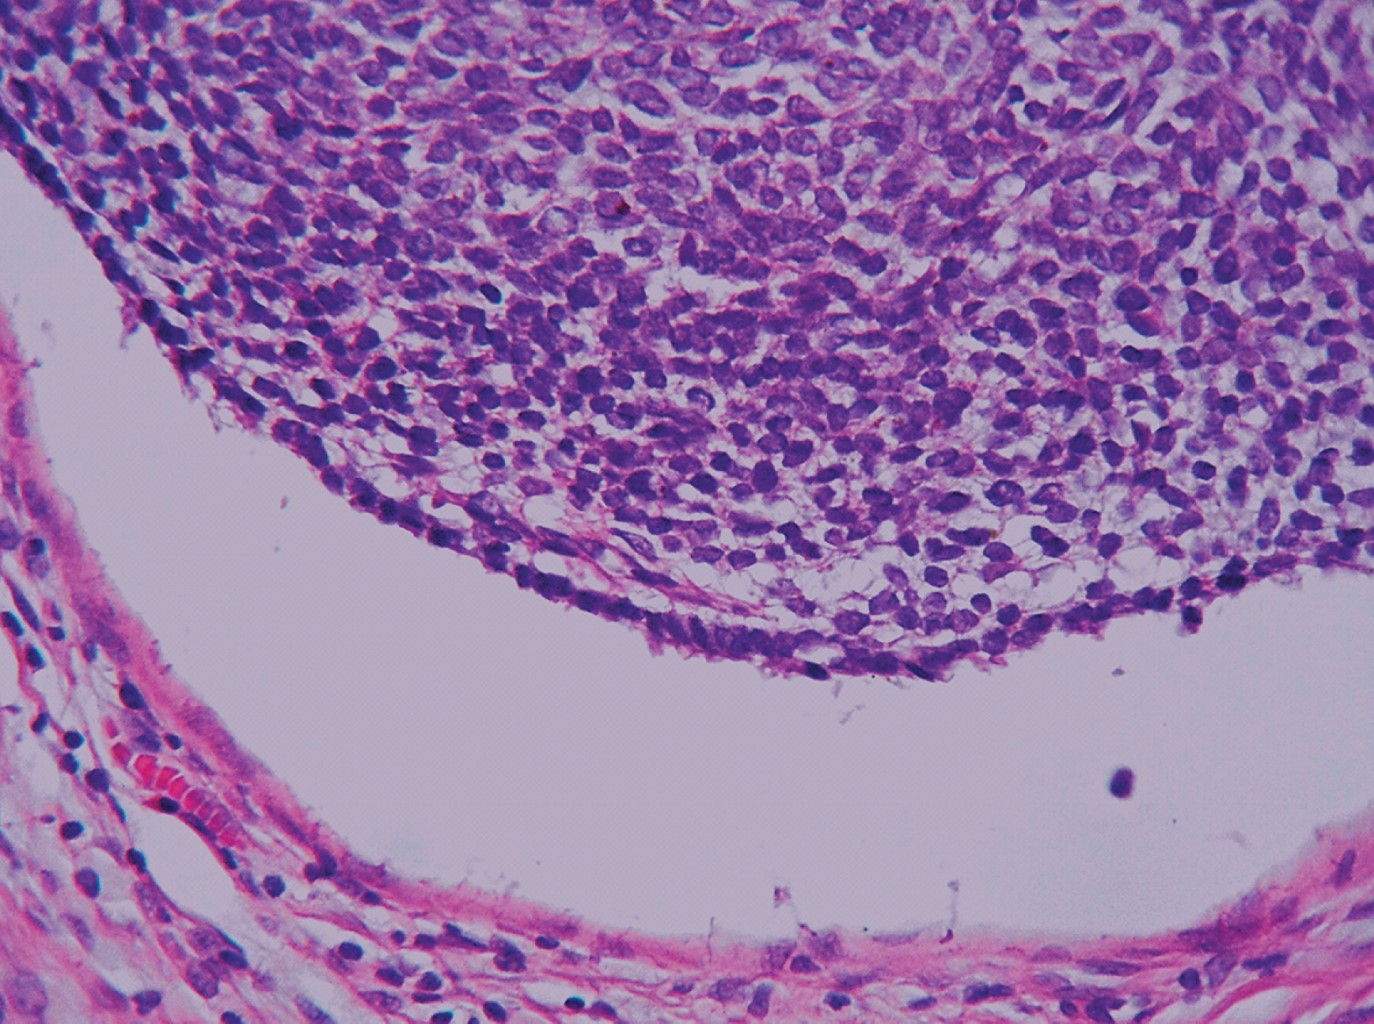

Figure 1

Figure 2

Figure 3

Figure 4

Figure 5